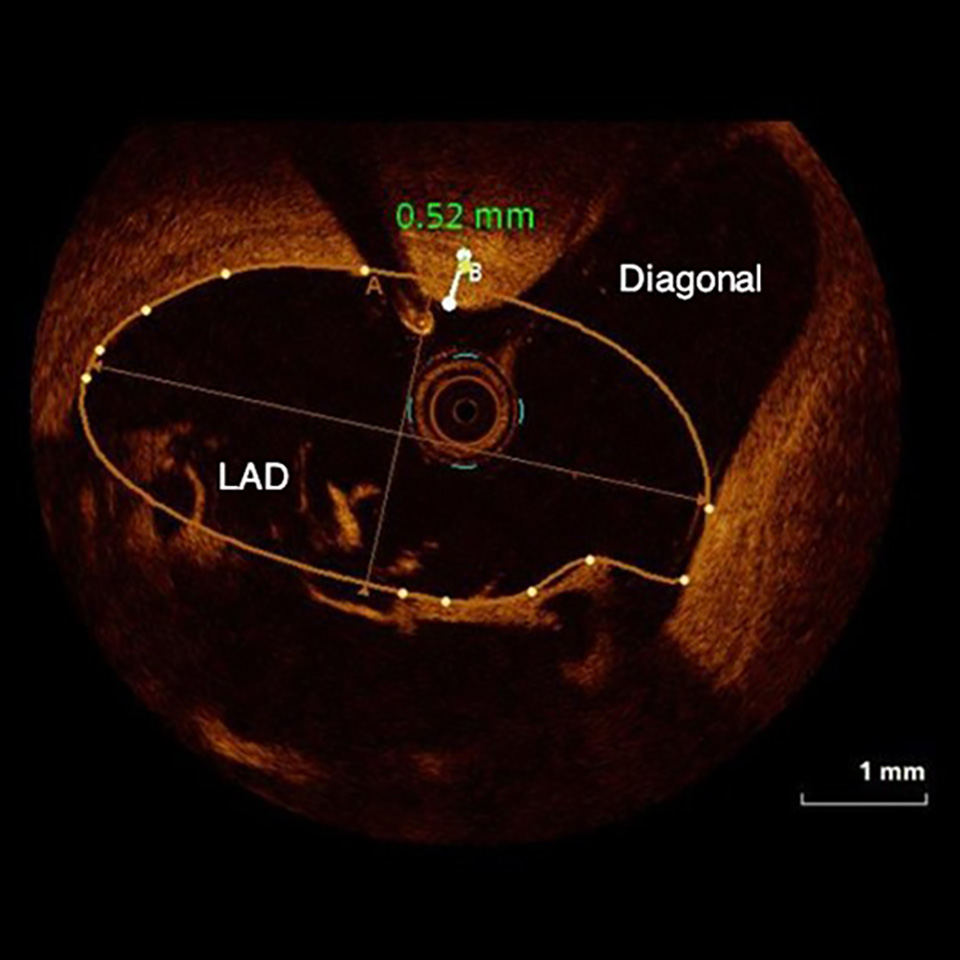

OPTICROSS HD Imaging Catheter 60 MHz

High-definition IVUS image of inside a coronary lesion using the OPTICROSS HD catheter

High-Definition IVUS image quality helps physicians more accurately identify lesion length, assess plaque morphology, and determine the tools required for vessel prep. See how OPTICROSS HD’s 60 MHz images stack up against the competition.

OPTICROSS versus OPTICROSS HD images courtesy of Michael Kim, MD, FACC, FSCAI North Colorado Medical Center

OPTICROSS HD versus OCT images courtesy of Massoud Leesar, MD; Professor of Medicine; Section Head, Interventional Cardiology, Baker-Dean Endowed Professor in Interventional Cardiology, University of Alabama-Birmingham